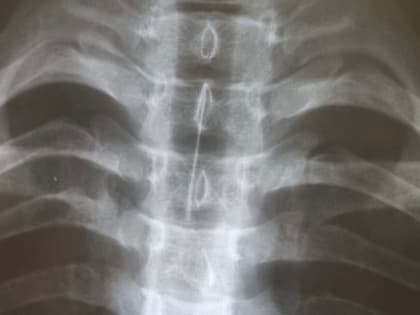

Хирурги Иркутской больницы извлекли из трахеи подростка иглу от шприца

Юного ангарчанина с инородным телом трахеобронхиального дерева экстренно доставили в Иркутскую областную детскую клиническую больницу в пять утра 17 февраля.